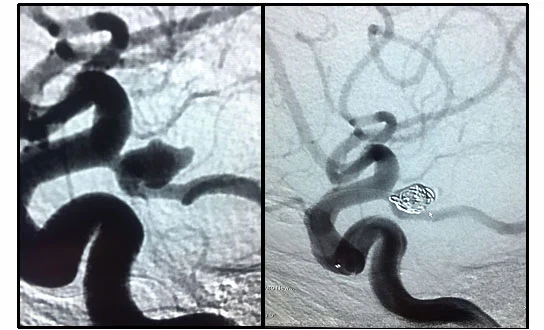

Trattamento endovascolare (embolizzazione): Questo trattamento consiste nel rilascio di filamenti metallici (spirali) all’interno dell’aneurisma per rallentare il flusso sanguigno e indurre la trombosi. Le spirali vengono introdotte tramite un microcatetere inserito nell’arteria femorale e guidato sotto controllo angiografico. In alcuni casi, è possibile inserire anche stent per mantenere il flusso sanguigno normale a valle dell’aneurisma.

Il trattamento dell’aneurisma cerebrale tramite intervento endovascolare, conosciuto anche come embolizzazione, è una tecnica innovativa che consente di trattare l’aneurisma senza necessità di un intervento chirurgico tradizionale. Questo trattamento prevede l’inserimento di un microcatetere attraverso l’arteria femorale (zona inguinale) per raggiungere il vaso cerebrale danneggiato, grazie al supporto del controllo angiografico. Una volta raggiunto l’aneurisma, vengono rilasciate spirali in platino all’interno della sacca aneurismatica per rallentare il flusso sanguigno e favorire la formazione di un coagulo, chiudendo così l’aneurisma.

Il trattamento endovascolare per aneurisma cerebrale ha il vantaggio di ridurre il rischio di rottura dell’aneurisma, ma in circa il 20% dei casi è necessario eseguire una seconda occlusione a distanza di tempo. Un’altra tecnica endovascolare utile è la Flow diversion, che prevede il posizionamento di una protesi metallica lungo l’arteria da cui origina l’aneurisma. Questa procedura ricostruisce la parete vascolare, isolando l’aneurisma e impedendo al sangue di fluire al suo interno. La Flow diversion è particolarmente indicata quando l’aneurisma presenta un colletto largo, ad esempio oltre 1 cm di diametro.

Embolizzazione aneurisma cerebrale con spirali in platino tramite intervento endovascolare